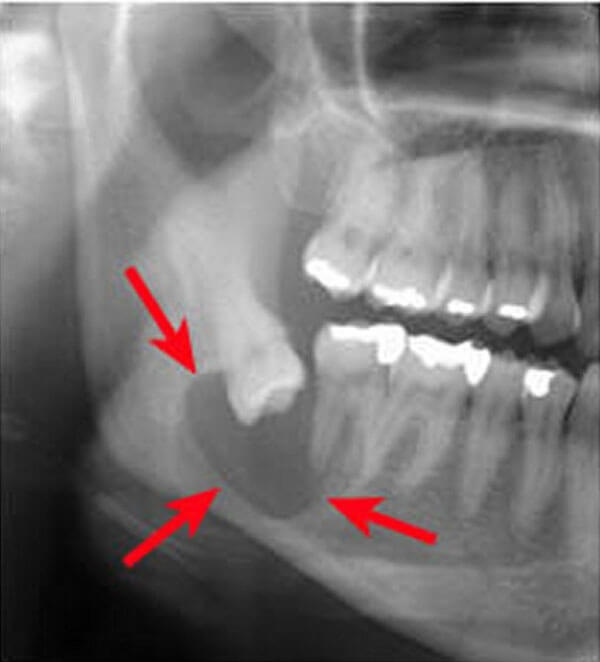

①顎の骨の中に発生する嚢胞